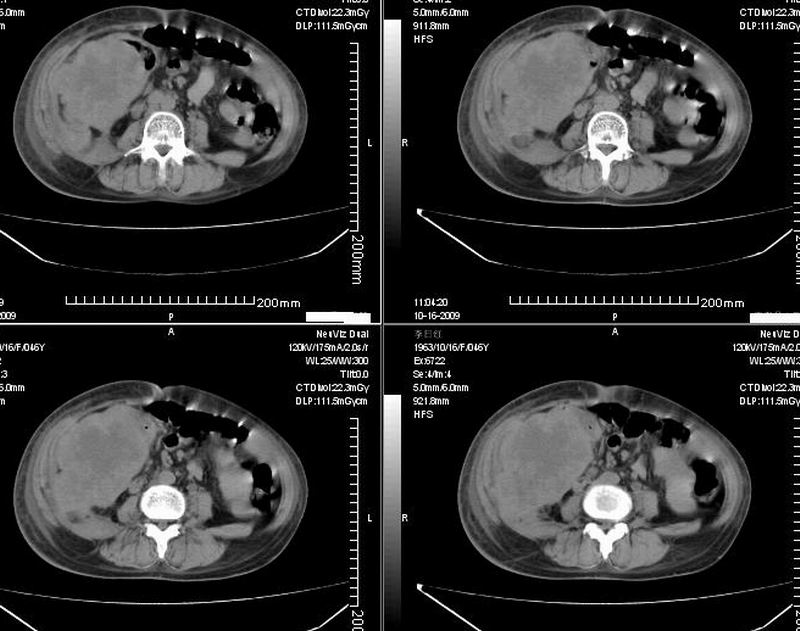

女:46y:一年前宫颈癌术后,现右下腹抚及肿块。

考虑宫颈癌术后复发周边侵犯/右中下腹及双侧腹股沟淋巴结转移。

考虑宫颈癌术后复发周边侵犯并右中下腹转移灶及双侧腹股沟淋巴结转移。